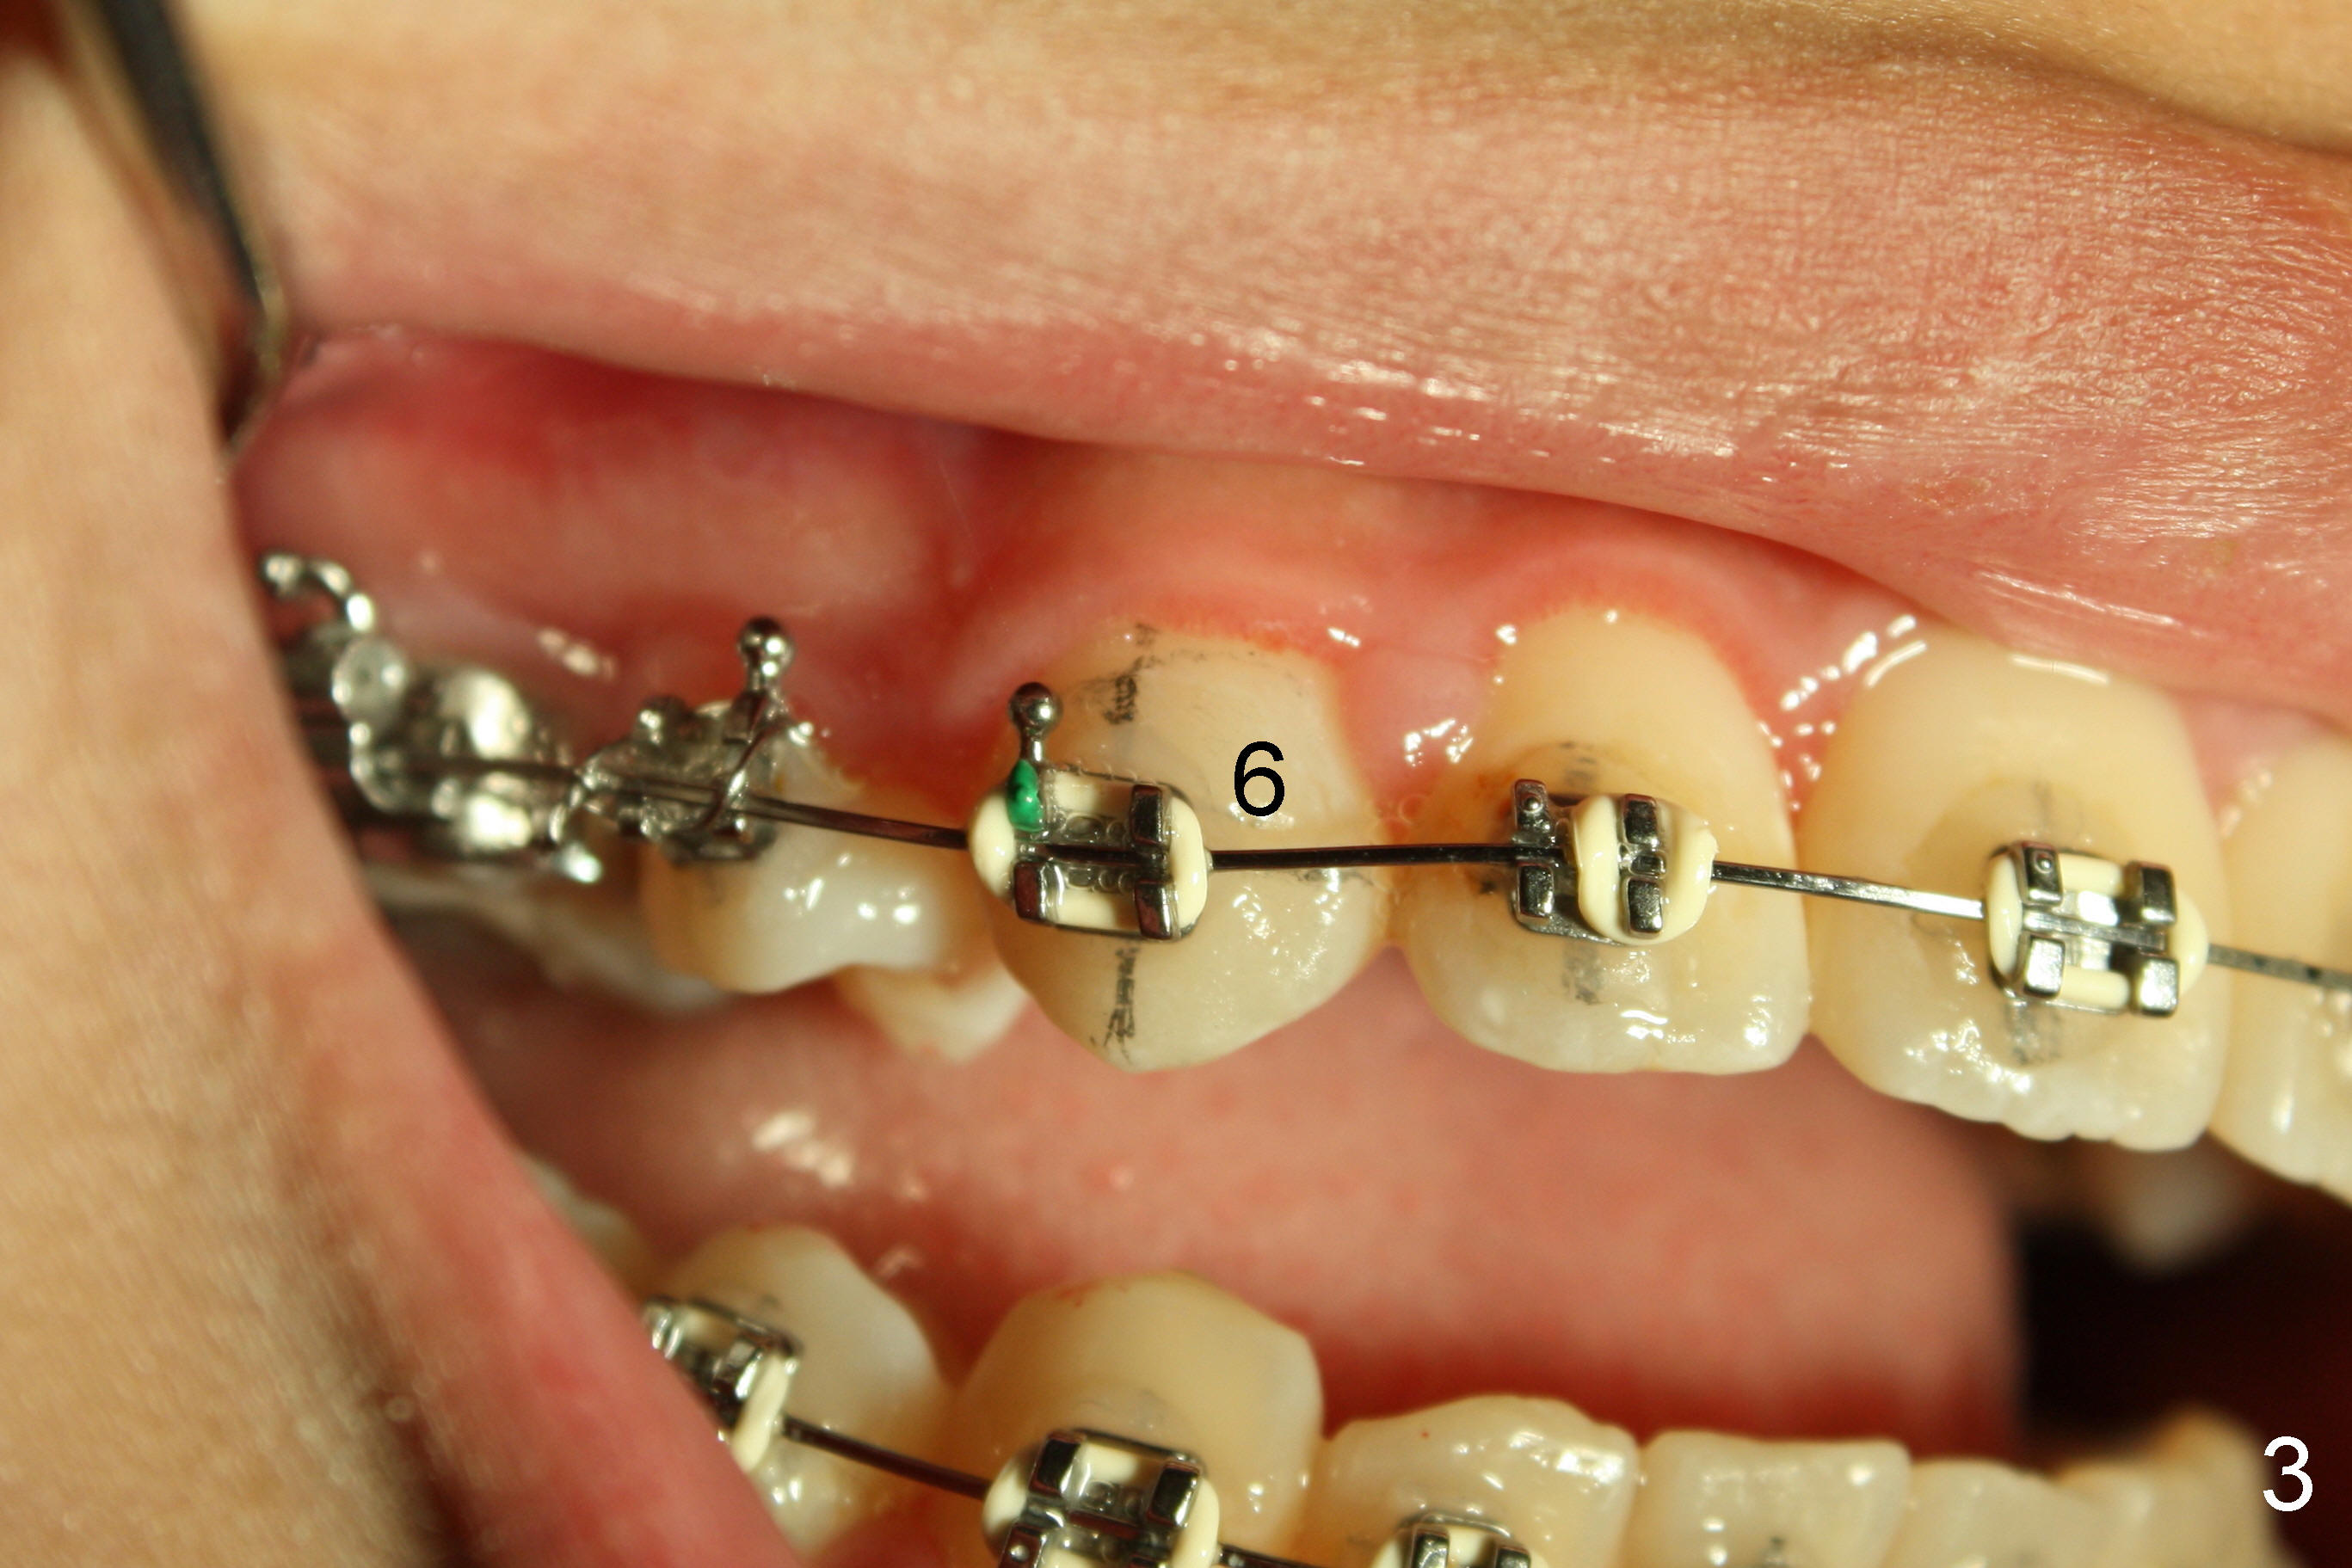

Christina has had the most complicated orthodontic treatment: phase one, mini-implant, extraction, and distalization. When canine Class I occlusion is achieved, anterior open bite is noted (Fig.1 between arrowheads). It is probably due to premature contact between the right upper and lower canines (Fig.2: #6, 27).